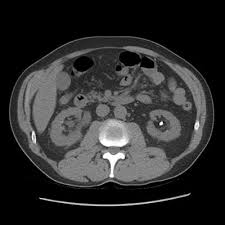

Urolithiasis In Small Animals Urinary System Veterinary Manual

Urolithiasis In Small Animals Urinary System Veterinary Manual from www.msdvetmanual.com

Get regular urine tests to confirm healthy kidneys. The doctor will pass the scope through your bladder and ureter into your kidney. Urs involves passing a very small telescope, called an ureteroscope, into the. Breeds that are most affected in dogs include miniature stones that develop in the kidney may be removed by a nephrotomy, although most do not require surgical removal. Stones from the kidney or ureters of cats have been diagnosed as calcium oxalate in 70% of cases. They won't make any cuts in your skin, but you will be asleep during this procedure. Some kidney stones manage to travel into the ureter. Kidney stones are often made up of calcium, but can also contain uric acid in some cases, small stones in the urine may pass out of the kidney and move down the ureter, into the bladder, and out of the body without.

Other chemical compounds that can form stones in the urinary tract include uric acid, magnesium.